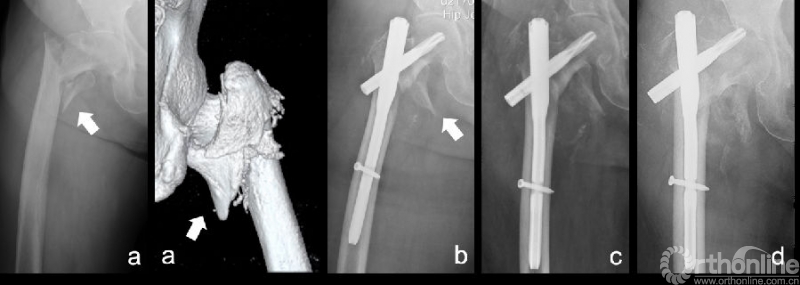

图3:82岁男性:(a)术前平片示右股骨粗隆间骨折,骨折AO/OTA分型为31 A2.1型,CT阅片明确内侧壁骨折为Ⅲ型。闭合复位后,(b)使用PFNA固定,未特意复位或固定内侧壁骨折块,术后可见内侧壁骨折块完全移位。术后1月常规复查时,平片(c)提示内侧壁骨折块位置无变化,仍移位明显。(d)术后3月时内固定切出。